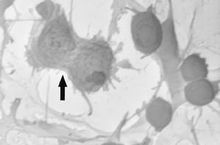

3)神經母細胞

成年人體中主要存在的神經幹細胞,分裂能力可以產生神經前體細胞和神經元和各類神經膠質細胞。

各類神經細胞的前體細胞,比如小膠質細胞是由神經膠質細胞前體產生的。